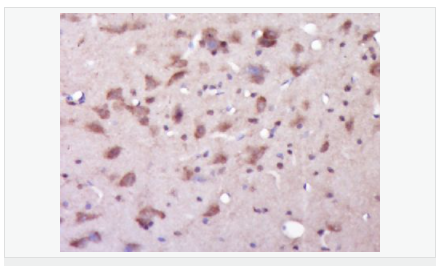

| 產(chǎn)品應(yīng)用 | WB=1:500-2000 ELISA=1:5000-10000 IHC-P=1:100-500 IHC-F=1:100-500 Flow-Cyt=1ug/test IF=1:100-500 (石蠟切片需做抗原修復(fù)) not yet tested in other applications. optimal dilutions/concentrations should be determined by the end user. |

| 產(chǎn)品介紹 | Alzheimer's disease (AD) patients with an inherited form of the disease carry mutations in the presenilin proteins (PSEN1; PSEN2) or in the amyloid precursor protein (APP). These disease-linked mutations result in increased production of the longer form of amyloid-beta (main component of amyloid deposits found in AD brains). Presenilins are postulated to regulate APP processing through their effects on gamma-secretase, an enzyme that cleaves APP. Also, it is thought that the presenilins are involved in the cleavage of the Notch receptor, such that they either directly regulate gamma-secretase activity or themselves are protease enzymes. Several alternatively spliced transcript variants encoding different isoforms have been identified for this gene, the full-length nature of only some have been determined. [provided by RefSeq, Aug 2008] Function: Probable catalytic subunit of the gamma-secretase complex, an endoprotease complex that catalyzes the intramembrane cleavage of integral membrane proteins such as Notch receptors and APP (beta-amyloid precursor protein). Requires the other members of the gamma-secretase complex to have a protease activity. May play a role in intracellular signaling and gene expression or in linking chromatin to the nuclear membrane. Stimulates cell-cell adhesion though its association with the E-cadherin/catenin complex. Under conditions of apoptosis or calcium influx, cleaves E-cadherin promoting the disassembly of the E-cadherin/catenin complex and increasing the pool of cytoplasmic beta-catenin, thus negatively regulating Wnt signaling. May also play a role in hematopoiesis. Subunit: Homodimer. Component of the gamma-secretase complex, a complex composed of a presenilin homodimer (PSEN1 or PSEN2), nicastrin (NCSTN), APH1 (APH1A or APH1B) and PEN2. Such minimal complex is sufficient for secretase activity. Other components which are associated with the complex include SLC25A64, SLC5A7, PHB and PSEN1 isoform 3. Predominantly heterodimer of a N-terminal (NTF) and a C-terminal (CTF) endoproteolytical fragment. Associates with proteolytic processed C-terminal fragments C83 and C99 of the amyloid precursor protein (APP). Associates with NOTCH1. Associates with cadherin/catenin adhesion complexes through direct binding to CDH1 or CDH2. Interaction with CDH1 stabilizes the complex and stimulates cell-cell aggregation. Interaction with CDH2 is essential for trafficking of CDH2 from the endoplasmic reticulum to the plasma membrane. Interacts with CTNND2, CTNNB1, HERPUD1, FLNA, FLNB, MTCH1, PKP4 and PARL. Interacts through its N-terminus with isoform 3 of GFAP. Interacts with DOCK3. Subcellular Location: Endoplasmic reticulum membrane; Multi-pass membrane protein. Golgi apparatus membrane; Multi-pass membrane protein. Cell surface. Note=Bound to NOTCH1 also at the cell surface. Colocalizes with CDH1/2 at sites of cell-cell contact. Colocalizes with CTNNB1 in the endoplasmic reticulum and the proximity of the plasma membrane. Also present in azurophil granules of neutrophils. Tissue Specificity: Expressed in a wide range of tissues including various regions of the brain, liver, spleen and lymph nodes. Post-translational modifications: Heterogeneous proteolytic processing generates N-terminal (NTF) and C-terminal (CTF) fragments of approximately 35 and 20 kDa, respectively. During apoptosis, the C-terminal fragment (CTF) is further cleaved by caspase-3 to produce the fragment, PS1-CTF12. After endoproteolysis, the C-terminal fragment (CTF) is phosphorylated on serine residues by PKA and/or PKC. Phosphorylation on Ser-346 inhibits endoproteolysis. DISEASE: Defects in PSEN1 are a cause of Alzheimer disease type 3 (AD3) [MIM:607822]. AD3 is a familial early-onset form of Alzheimer disease. Alzheimer disease is a neurodegenerative disorder characterized by progressive dementia, loss of cognitive abilities, and deposition of fibrillar amyloid proteins as intraneuronal neurofibrillary tangles, extracellular amyloid plaques and vascular amyloid deposits. The major constituent of these plaques is the neurotoxic amyloid-beta-APP 40-42 peptide (s), derived proteolytically from the transmembrane precursor protein APP by sequential secretase processing. The cytotoxic C-terminal fragments (CTFs) and the caspase-cleaved products such as C31 derived from APP, are also implicated in neuronal death. Defects in PSEN1 are a cause of frontotemporal dementia (FTD) [MIM:600274]. Similarity: Belongs to the peptidase A22A family. SWISS: P49768 Gene ID: 5663 Database links: Entrez Gene: 5663 Human Entrez Gene: 19164 Mouse Omim: 104311 Human SwissProt: P49768 Human SwissProt: P49769 Mouse Unigene: 3260 Human Unigene: 998 Mouse Unigene: 44440 Rat Important Note: This product as supplied is intended for research use only, not for use in human, therapeutic or diagnostic applications. 此抗體識別分子量為45-50kDa早老素蛋白-1。PS-1主要在神經(jīng)細(xì)胞中表達(dá),早老蛋白集中于體細(xì)胞和樹突狀細(xì)胞中。相反,再早發(fā)家族AD(FAD)中和散發(fā)AD病人中,PS1免疫反應(yīng)出現(xiàn)在老年斑和神經(jīng)纖維纏結(jié)的神經(jīng)炎中。 |